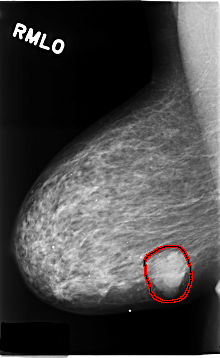

C_0184_1.RIGHT_MLO

RIGHT_MLO LINES 4648 PIXELS_PER_LINE 2856 BITS_PER_PIXEL 12 RESOLUTION 50 OVERLAY

FILE: C_0184_1.RIGHT_MLO.OVERLAY

TOTAL_ABNORMALITIES 1

ABNORMALITY 1

LESION_TYPE MASS SHAPE LOBULATED MARGINS MICROLOBULATED

ASSESSMENT 5

SUBTLETY 5

PATHOLOGY MALIGNANT

TOTAL_OUTLINES 1

BOUNDARY